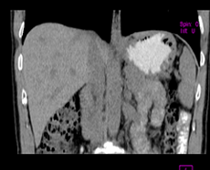

患者,男,57,常年不吃午饭,近一个月来腹部隐痛,无明显黄疸,明天进行增强扫描,图象另上传,麻烦各位帮忙一起看看讨论讨论

肝外胆管扩张,胰头增大,肠系膜上静脉似有包埋征象。

考虑:胰头占位性病变,建议增强进一步检查。

肝内外胆管扩张,胆管未端阻塞,建议mri检查

考虑肝总管或胆总管占位性病变,建议mrcp或ercp.

胰头占位可能性大!建议增强!

胰头增大,胆总管增宽,考虑胰头癌可能性大,明天看增强片有助诊断.